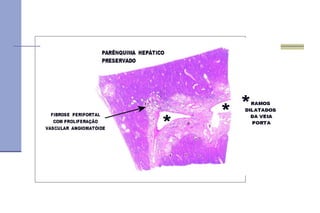

Fibrose periportal   Definição :  neoformação conjuntivo vascular nos espaços porta biliares, com perturbação da circulação portal.  Não ocorre subversão da arquitetura lobular Fibrose secundária a esquistossomose. Poderia evoluir para a cirrose??

Macroscopia :  fibrose periportal.  Aspecto 'em haste de cachimbo de barro branco' ( clay pipestem cirrhosis  ou fibrose hepática de Symmers -Bogliolo).

Fibrose   Microscopia :   neoformação fibrótica periportal peripileflebite. intensa proliferação vascular angiomatóide. pigmento esquistossomótico ( células de Kupffer com pigmentação negra do citoplasma)   moderado infiltrado inflamatório crônico ( granulamatoso ou não).  parênquima mantém a estrutura lobular mais ou menos intacta. gigantócitos contendo ovos de  Schistosoma mansoni  (na maior parte, fragmentos de cascas).